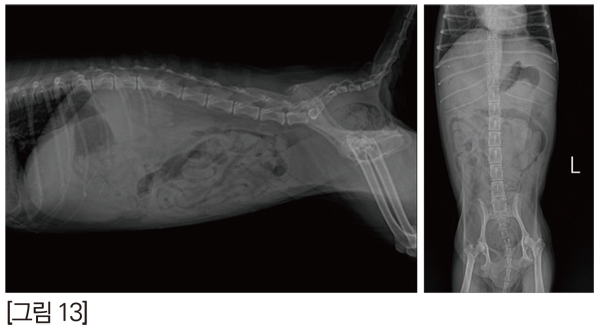

VD상에서 mass로 의심될만한 소견이 있지만, 위 내 음식물과 감별하기는 힘들었습니다. [그림 13]